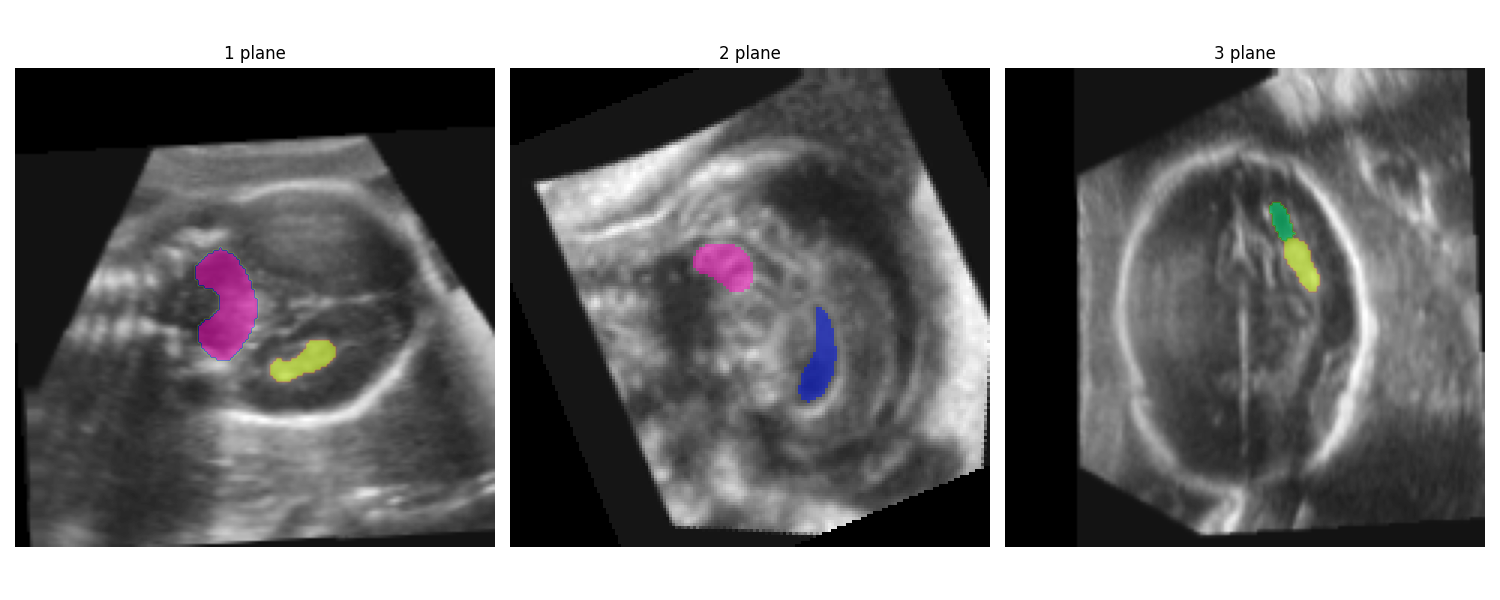

Running this results in the following output figure (CB: pink, ChP: yellow, LPVH: green, CSPV: blue):

image aligned to the atlas coordinate system with a subcortical segmentation overlay.